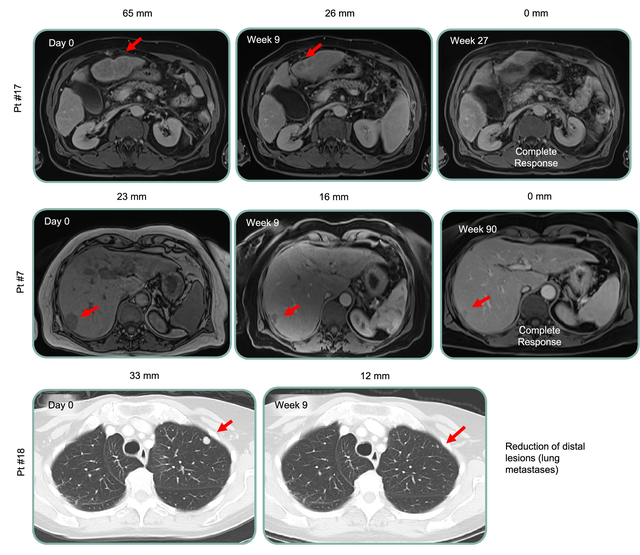

典型病例

患者11在接受联合治疗后,肝脏肿瘤持续缩小-第18周时肿瘤缩小59%,表明治疗可能带来长期获益。

其他代表性临床反应如下: